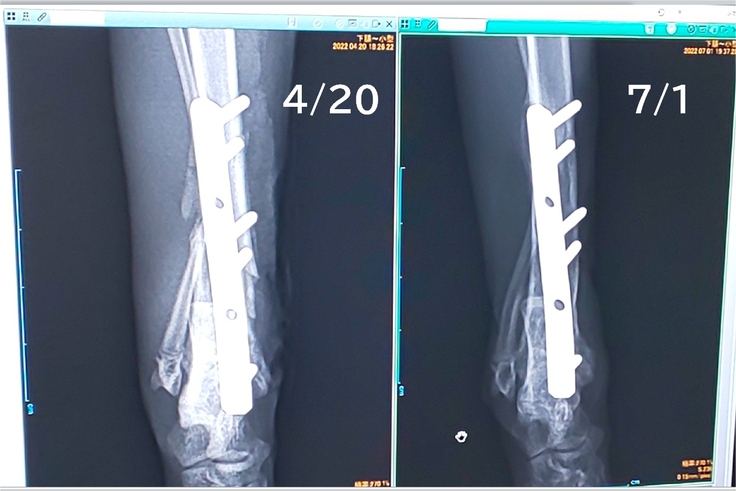

骨の調子は…「若いだけあって回復が早いね」いただきました👏✨

素人目にはよくわかりませんが、骨が太くなっていることだけわかります。

いよいよ、7月7日、プレート除去の予約をして参りました。

6本のボルトで固定している場合、スタンダードなのは1度で外すと穴だらけで再骨折の可能性が出てしまうため、2回に分けて外すそうです。

ただ、ガッツくんは成長期。プレートの上に骨がかぶりかけているため、1度で外した方が良いかもしれないそうです。

【赤丸の箇所:プレートの上に白くモヤっぽいのが再生中の骨らしいです】

1回目の手術の時に、様子を見て決めていただくことになりました。

こればっかりは先生にお任せするしかありません(>_<)